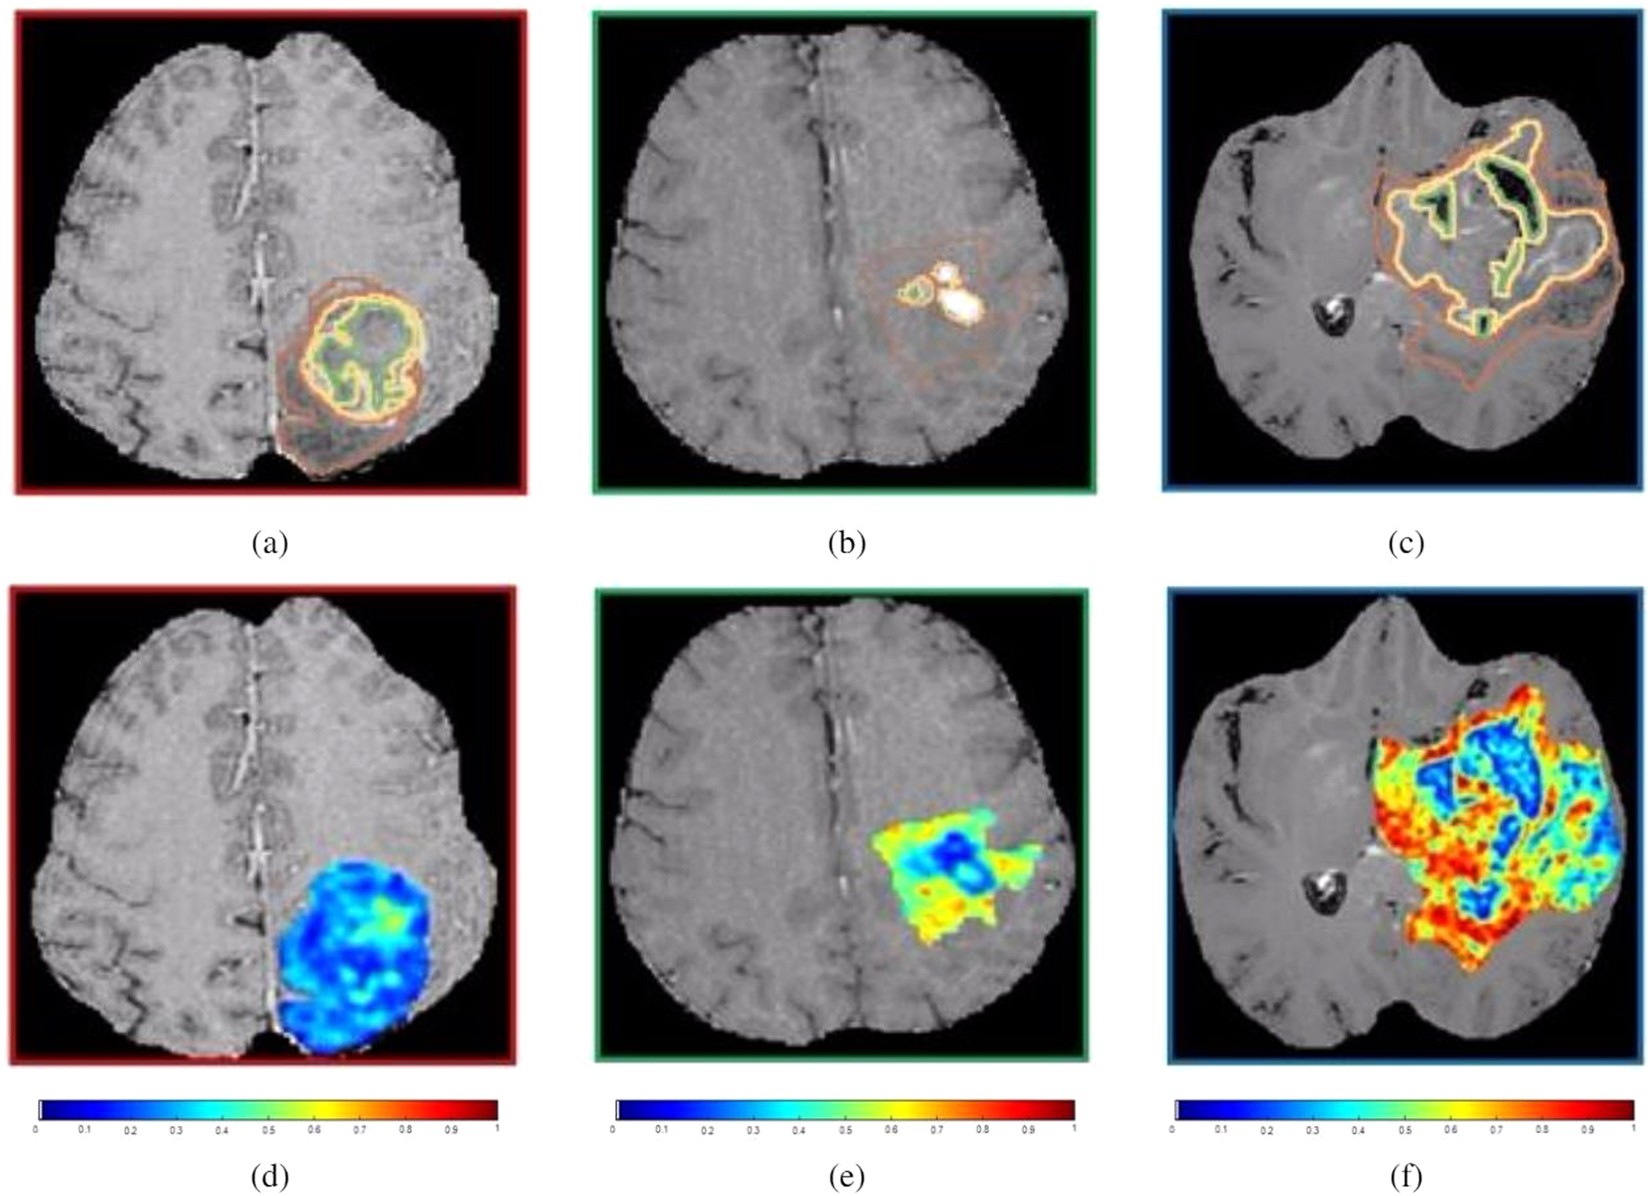

Figure 3

(a)–(c) show a 2D Gd-T1w MRI slice with expert-annotated necrosis (outlined in green), enhancing tumor (yellow) and edematous regions (brown) in 3 different GBM patients that exhibited low, medium, and high HES respectively. The corresponding Haralick feature map has been overlaid on the manually annotated tumor regions, for HES low (d), HES medium (e), and HES high (f).